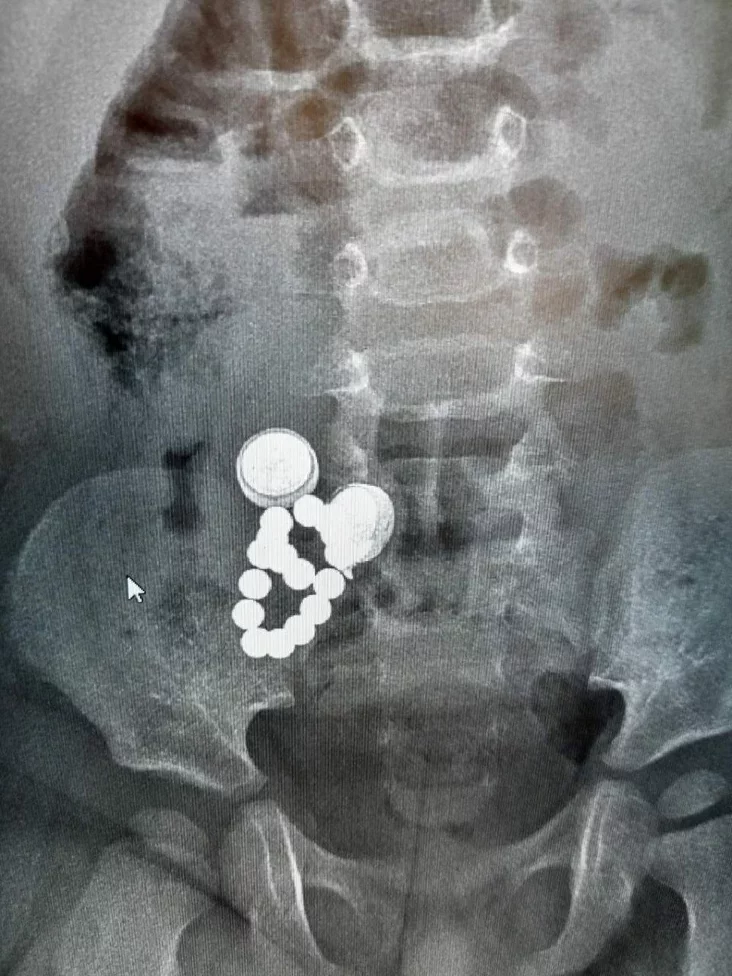

Фота: t.me/guzo_v

Дзіця ўзростам усяго 1,8 года было шпіталізаванае ў Дубровенскую бальніцу са страўнікава-кішачным крывацёкам. Пры абследаванні аказалася, што ў яго страўніку і кішэчніку аказаліся 2 батарэйкі, 16 магнітаў і шруб.

Дзіця экстранна прааперавалі і яно цяпер лечыцца ў аддзяленні хірургіі.